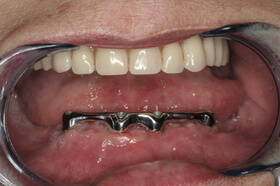

A kezelés végén a fogszabályozó készülék eltávolítása előtt